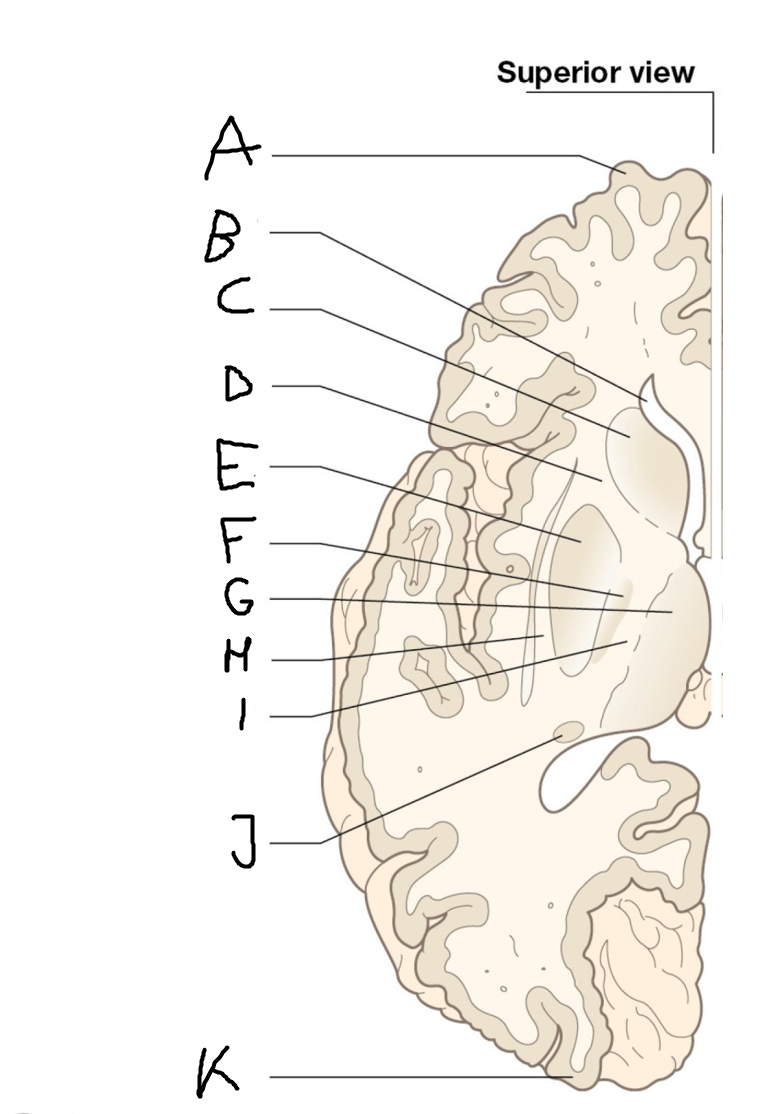

internal capsule (posterior limb)

B

anterior horn of lateral ventricle

C

head of caudate nucleus

D

internal capsule (anterior limb)

E

putamen

F

globus pallidus

G

Thalamus

H

External capsule

I

internal capsule (posterior limb)

J

tail of caudate nucleus